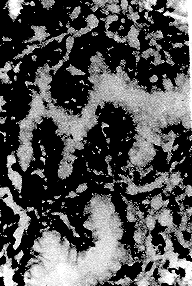

2.2 胃切除标本20例共切片65张,均未见上述胃镜活检标本中所见胃腺体的套管现象,甚至连无定型内涵物也难以找到。但在腺体增生区域可见具有纤维血管轴心的乳头状结构(图5)。

图5 胃癌切除标本,癌旁粘膜腺内有带纤维血管

轴心的乳头(×400)